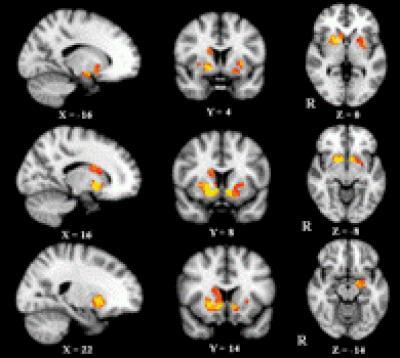

In low back pain patients, increased gray matter volume was observed in the bilateral putamen and nucleus accumbens, the left amygdala, the right caudate nucleus and the pallidum revealed by region of interest voxel-based morphometry analyses.

(Photo Credit: Neural Regeneration Research)